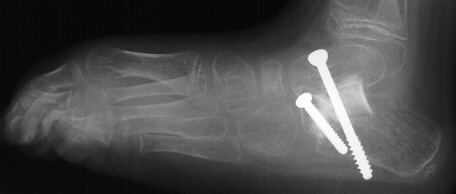

The patient failed conservative management with bracing and therefore

had a bilateral subtalar arthrodesis with lateral column lengthening and

gastrocnemius lengthening

.

Post-operatively, the patient was placed in bilateral short leg casts and

allowed full weight bearing.

Postoperative X-rays:

- Left Talocalcaneal angle is 24 degrees, Talonavicular angle is 2 degrees

- Right Talocalcaneal angle is 28 degrees, Talonavicular angle is 2 degrees